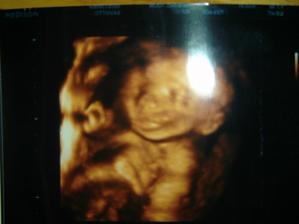

1/12/08: byli jsme na 3D ultrazvuku, miminko už nebylo tak klidné jako na předchozích UTZ, nedalo se pomalu ani zachytit, ale bude to prý z 95% holčička, máme radost!!!!!!!!! Je to pěkná čahounka (asi po mně🙂)), měří 20cm, váží 215g.